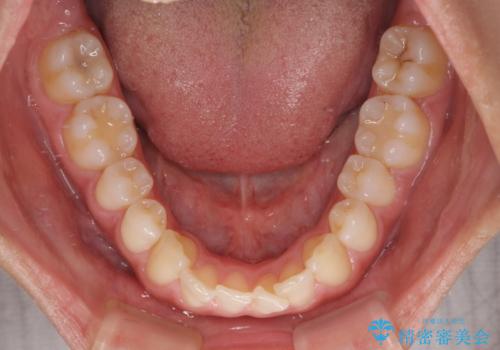

前歯の重なりをインビザライン・モデレートで矯正治療

- 上下前歯の重なりを気にして来院された患者様です。

安価なインビザラインパッケージを用いての治療を希望されており、デコボコの程度が中等度であったため、インビザライン・モデレートを用いて矯正治療を行うこととしました。